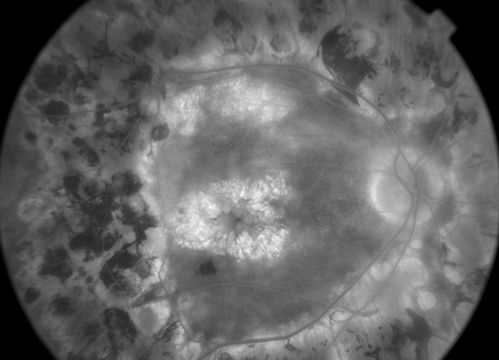

late phase FA

50+ YO female presented with DM type 1;

PT presented with PDR s/p extensive PRP

FA showed CNV OD

VA stable at 20/150 for 1 year